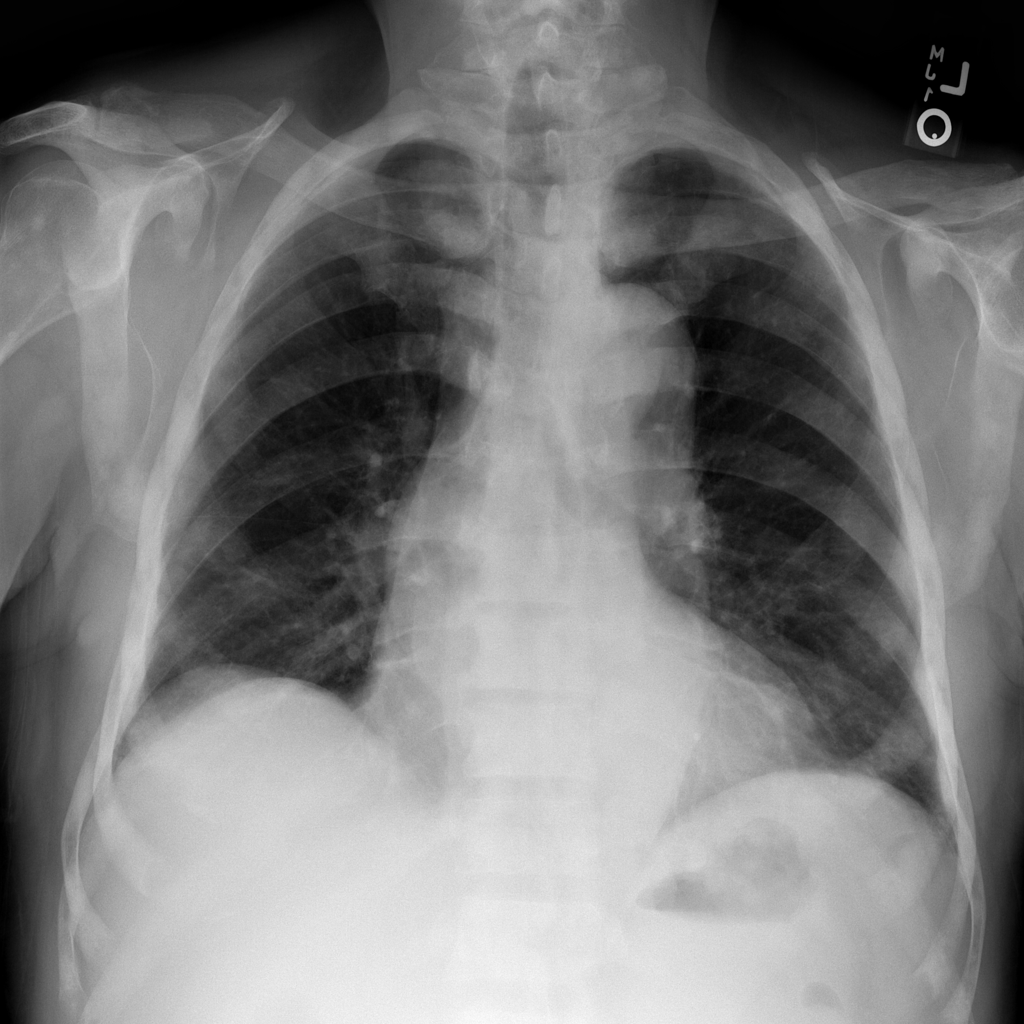

Combine images into a multidimensional array to demonstrate progression¶

In the next example, instead of 1 image you’ll use 9 X-ray 1024x1024-pixel

images from the ChestX-ray8 dataset that have been downloaded and extracted

from one of the dataset files. They are numbered from ...000.png to

...008.png and let’s assume they belong to the same patient.

3. You can now display the “health progress” by plotting each of frames next to each other using Matplotlib:

fig, axes = plt.subplots(nrows=1, ncols=num_imgs, figsize=(30, 30))

for img, ax in zip(combined_xray_images_1, axes):

ax.imshow(img, cmap='gray')

ax.axis('off')